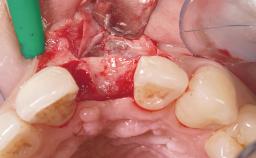

A 42-year-old female patient was referred to our clinic at the School of Dentistry of the University of São Paulo in November 2004, presenting a deficient restoration in the upper left central incisor. The clinical examination revealed no gingival retraction or any signs of gingival inflammation and, therefore, previous periodontal treatment was not considered. The patient presented a high lip line at full smile and a thin tissue biotype. This combination characterized a high-risk situation from an anatomic point of view, which required careful preoperative planning and cautious surgical execution.

Placement Protocol Immediate implant placement

Tooth Site Maxillary incisor or canine

Loading Protocol Immediate